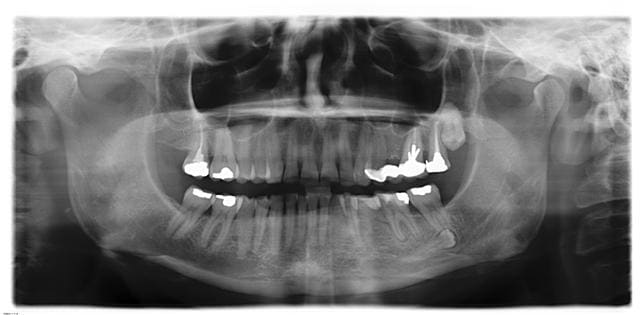

Je l'accrocherais bien dans mon salon...

cette PM est mignonne comme tout.